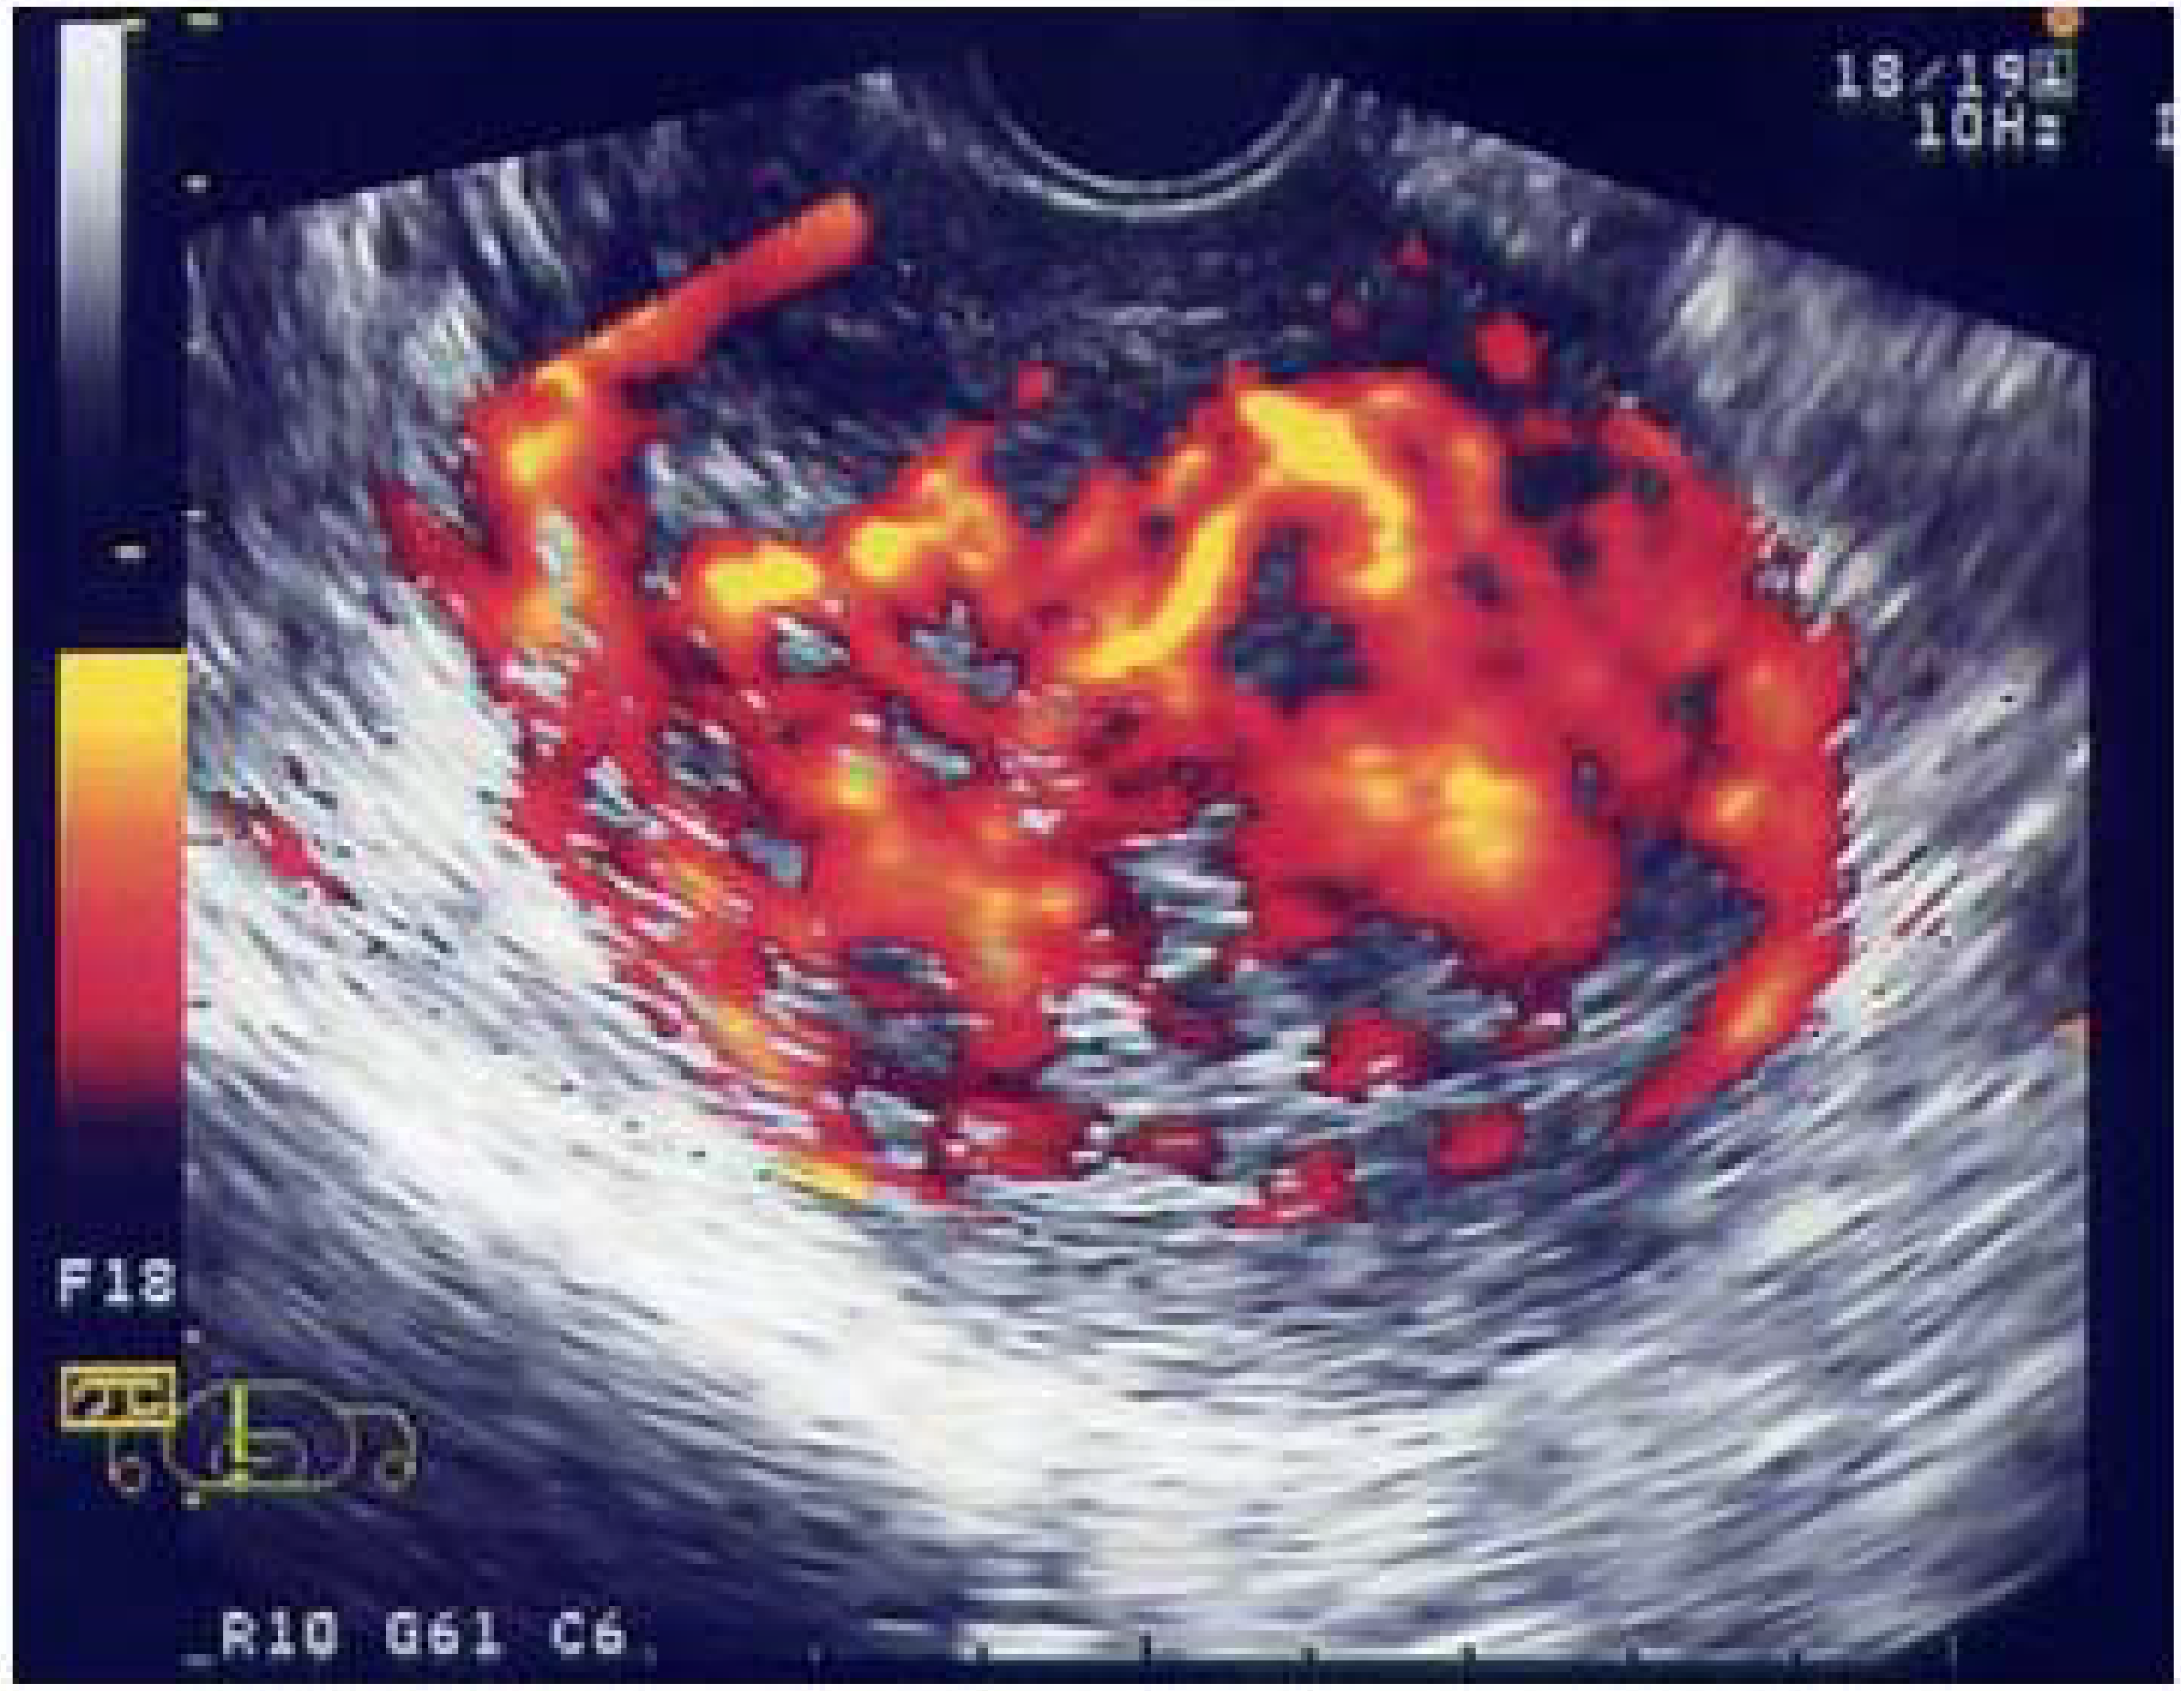

It has been revealed that angiogenesis plays one of the most important roles in the multiplication of cancer cells and tumor development, which was an epoch-making event in cancer biology in recent years. Furthermore, it has also been discovered that vascular endothelial growth factor (VEGF), in which tumor cells are produced under a low oxygen environment, is the key controlling factor in inducing tumor angiogenesis [14]. Subsequently, the treatment method of starving cancer by controlling angiogenesis has promptly developed further, leading to the clinical approval for the first time in the world of Bevacizumab, an anti-angiogenesis drug, against colorectal cancer. We focused on uterine cancer sarcoma/uterine sarcoma which is an intractable cancer among gynecologic tumors and reported that the angiogenesis of this tumor was extremely intense compared with other uterine cancers (Figure 2) [15,16]. These tumors are extremely malignant among human solid cancers, being a disease with adverse prognosis which shows strong resistance to conventional chemotherapy or radiation therapy. Taking this into consideration, we dared to position this tumor as the subject model of ultrasound treatment and implemented a basic study on angiogenesis suppressive therapy (fumagillin derivative: using TNP-470) by concomitantly using low-intensity ultrasound for the first time [8].

Figure 2.

Potential blood flow (angiogenesis) of malignant tumors is enhanced and extracted using color Doppler ultrasound imaging. This picture is a clinical case of uterine sarcoma, using Levovist. Because uterine sarcomas have the most aggressive angiogenesis among all uterine cancers, they are used as a model for angiogenesis.